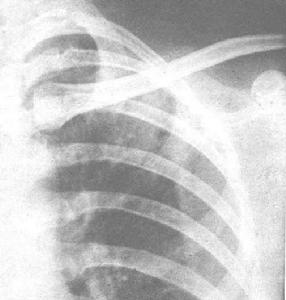

肺諾卡菌病X線圖起病緩急不一。免疫功能低下者常呈急性起病。全身症狀有發熱,疲乏無力,厭食等。呼吸道症狀有咳嗽,黏稠膿痰,量通常不多,胸痛,氣急,咯血等。胸壁有時可見瘺管。不治療或治療延誤則轉成慢性,出現類似肺結核病的慢性感染的相應表現。胸部X線呈現炎症浸潤、實變、單發或多髮結節狀陰影,經常有膿腫和空洞形成,偶見厚壁空洞。病變分布以

臨床症狀初為乾咳,繼之為粘稠膿性痰,後期咳膿臭痰,痰中可帶血,常有發熱、盜汗、胸痛及消瘦等,體溫多為38~C~40~C。可出現胸腔積液或膿胸,少數可穿破胸壁至皮膚形成瘺管,也可波及腹腔、內臟或經血循環播散至全身。x線胸片早期表現為炎性浸潤類似小葉性或大葉性肺炎,也可表現為單發或多髮結節影,可發現厚壁透光區,代表多發性小膿腫形成的空洞。還可伴有肺門淋巴結腫大,但很少有鈣化。病變可累及一葉或多葉。有時呈水皰性或壞疽性改變,表麵皮膚為粉紅色,其後迅速擴展並破潰,其上有粘性黃白色膿液;向周圍擴散後引起全足腫脹,足趾變形。也可向深部組織及骨擴展,形成多數膿腫、相互交通的竇道、瘺管及骨質破壞等。分泌物呈漿液狀、膿性或油狀,常帶白色、黃色或黑色顆粒。病原菌最常播散部位是在大腦引起腦膿腫,其次是在腎臟引起腎膿腫等,也可引起心內膜炎、心肌炎、心包炎,肝、脾、腎上腺、胃腸、淋巴結、肋骨、椎骨、骨盆及關節也可受累,胰腺、甲狀腺、眼、耳、脊椎、垂體及膀胱較少累及。病變以局部膿腫最為常見。臨床感染徵象突出,常有發熱,多部位膿腫,多器官損害,預後不良。臨床診斷本病臨床表現無特異性,如有前述部位感染徵象而排除其他疾病時可考慮本病的可能性。尤其是臨床上同時有“腦瘤”或多發性皮膚膿腫者,更應考慮血行播散性諾卡菌病,及時進行諾卡菌病原學檢查確診。

其他輔助檢查:胸部X 線呈現炎症浸潤、實變、單發或多髮結節狀陰影,經常有膿腫和空洞形成,偶見厚壁空洞。病變分布以兩下葉多見,亦可呈粟粒樣或瀰漫性間質性浸潤,極少鈣化和纖維化,約1/3 患者並發膿胸。